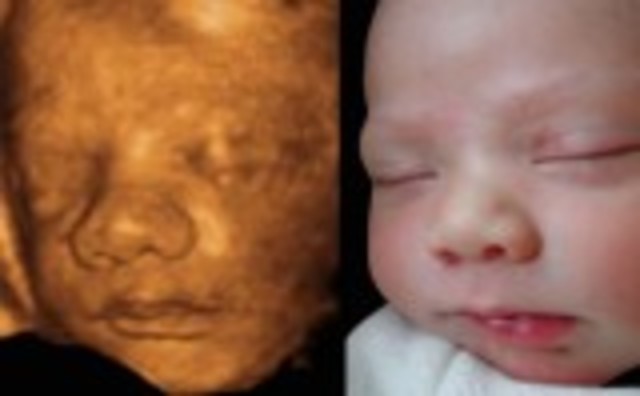

• Week Ten: Embryo is Now a Fetus

Week Ten: Embryo is Now a Fetus

The embryo is now called a fetus. The muscles are mostly developed.The fingerprint can now be seen.